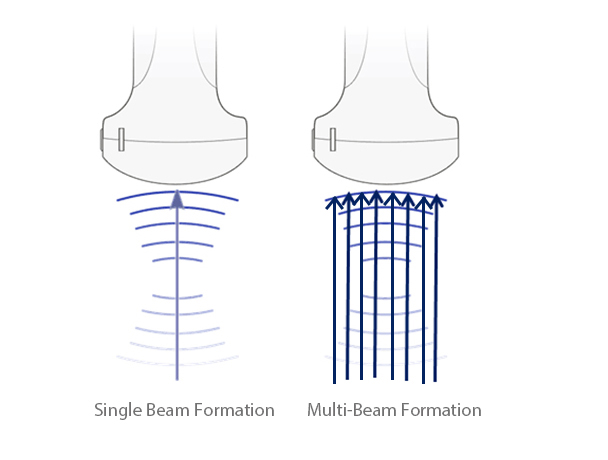

Multiple Beam Formation

Maximum of eight times tasking of one transmitted beam, resulting in excellent time resolution and higher frame rate.